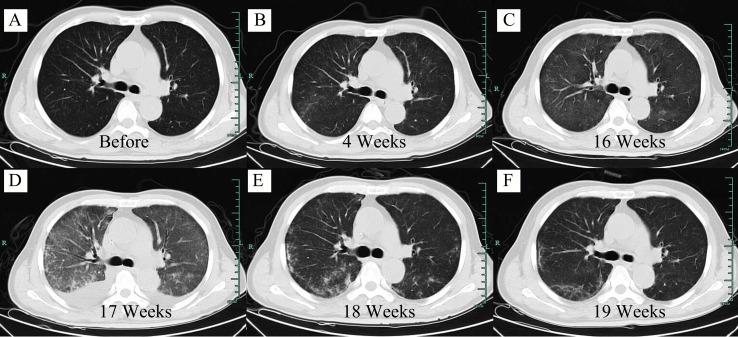

A 63-year-old male patient with refractory EBV-positive diffuse large B-cell lymphoma, developed interstitial pneumonitis with prolonged hypoxemia at 16 weeks after CD19 CAR-T cell therapy. There was no evidence of CRS and any infections. The patient recovered after intravenous immunoglobulin without tocilizumab or glucocorticoid administration. Now he is still in remission without interstitial pneumonitis 3 years after CAR-T cell therapy.

一名 63 岁男性患者患有难治性 EBV 阳性弥漫性大 B 细胞淋巴瘤,在 CD19 CAR-T 细胞治疗后 16 周出现间质性肺炎伴长时间低氧血症。没有 CRS 和任何感染的证据。患者在未使用托珠单抗或糖皮质激素的情况下接受静脉注射免疫球蛋白后康复。现在,CAR-T 细胞治疗 3 年后,他仍然没有间质性肺炎,处于缓解状态。